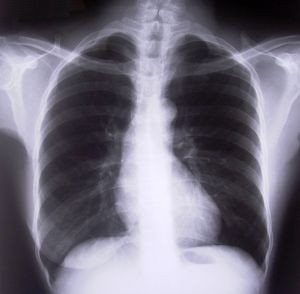

chest-xray-d000000601a3fd155e52b

A tüdőrák a tüdő szövetén belül a daganatos, abnormálisan fejlődő sejtek elszaporodásának következménye. E sejtek jóval gyorsabban szaporodnak, mint a szervezet normális sejtállománya. Az abnormálisan fejlődő sejtek összecsapzódnak, szabálytalanul burjánzó tumortömeget hoznak létre. Ha a sejtek szabálytalan növekedése a tüdőben kezdődik, akkor beszélünk ún. primer, azaz elsődleges tüdődaganatról, tüdőrákról.